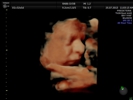

Fotografías de ecografías 4D HD/5D

Haga click sobre las imágenes para ampliar